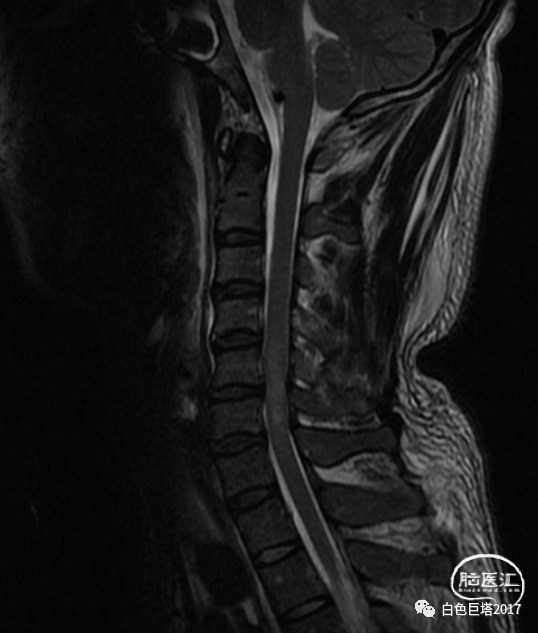

患者苏某,34岁男性,因“高处坠落致意识障碍1小时余”入院。患者自8米高处坠落,头面部着地,入院时头面创口、口腔、鼻腔流血不止,GCS E2V1M5为8分。很快出现血压下降至70/52mmHg、血氧下降85%。急诊气管插管,完善头颅、颈椎、胸腹部CT检查,提示颌面、颅底多发骨折、鼻腔积血,软组织挫裂伤,左颞颌关节脱位,牙齿缺失。额骨骨折、右额顶叶脑挫裂伤、蛛网膜下腔出血,颅内积气。颈椎间盘突出、颈椎退行性变、未见明显骨折。双侧1-2肋骨骨折,T5-7左侧横突骨折;双肺挫伤;左侧少量气胸。腹腔脏器未见明显损伤表现。